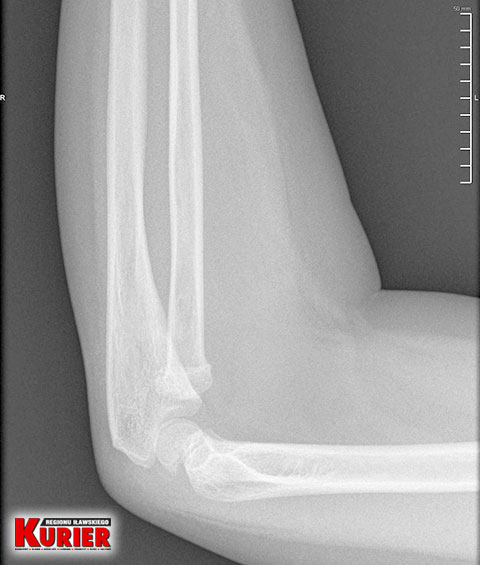

– Zaniepokoiło mnie to, że pani doktor zleciła wykonanie prześwietlenia przedramienia, a nie łokcia, choć to z nim był największy problem – opowiadała nam wtedy kobieta. – Pani, która wykonywała prześwietlenie, na moją prośbę załapała łokieć, choć nie powinna. Powiedziała, że widzi złamanie, ale to lekarz zdecyduje, co dalej. Pani doktor stwierdziła jedynie stłuczenie. Zapytała Szymona, czy chce, żeby mu włożyć rękę w szynę. Syn zrobił duże oczy i był przerażony. Oczywiście tego nie chciał, więc tego nie zrobiono.

– Tu pan doktor, w odróżnieniu do lekarki w Iławie, zlecił wykonanie prześwietlenia jednej i drugiej ręki, dla porównania – opowiadała nam pani Karolina. – Gdy tylko zobaczył zdjęcie, od razu stwierdził złamanie łokcia z przemieszczeniem. Nie było już pytania, czy dziecko chce mieć założoną szynę czy nie. Od razu to zrobiono i skierowano nas do Olsztyna.

– Pytałam tam doktora, czy na zdjęciu z prześwietlenia w Iławie widać złamanie – mówiła w rozmowie z nami kobieta. – Oczywiście potwierdził i pokazał mi nawet, gdzie dokładnie do niego doszło. Konieczna była prawie godzinna operacja, podczas której ustabilizowano rękę drutem. Przeprowadzono ją od razu, bo lekarz mówił, że każda minuta w tym stanie jest na niekorzyść dziecka.

„W RTG bez ewidentnych cech świeżego urazu.

Zalecenia: opatrunki z Altacetem, okłady z lodu,

oszczędzanie”

– czytamy w wypisie z iławskiego szpitala

W iławskim szpitalu dziecku wykonano prześwietlenie

jednej ręki i dopatrzono się jedynie stłuczenia

W nowomiejskim szpitalu dla porównania

wykonano prześwietlenie obu rąk i stwierdzono

w lewej złamanie łokcia z przemieszczeniem